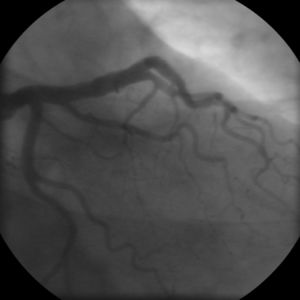

يمكن اعتبار مرض تصلب شرايين القلب مجموعة من الأمراض التي تصيب القلب. واحدة من هذه صور هذا المرض هو شخص بلا أعراض وجدران شرايين قلبه التاجية مبطنة من الداخل بخطوط من الدهون atheromatous streaks. يمثل ظهور هذه الخطوط المرحلة الأولى من مرض القلب التاجي ولكنها لا تعيق تدفق الدم خلال الشريان. إذا تم عمل تصوير الشرايين التاجية Coronary Angiogram خلال هذه المرحلة من المرض فانه من المحتمل ألا يظهر أي دليل على وجود مرض تصلب الشرايين القلبية وذلك لان قطر تجويف الشريان لم يقل. خلال عدة سنوات، تزداد هذه الخطوط الدهنية سماكة، وازدياد سماكتها مبطِنة جدار الشريان يؤدي في النهاية إلى صغر تجويفه وبالتالي يعوق مسار الدم خلاله. اُعتقد في السابق أن عملية تكوّن الصفائح الدهنية عملية بطيئة وتدريجية، لكن ظهرت دلائل حديثة على أن التكون التدريجي لهذه الصفائح يُسرّعُه تمزقات صغيرة تحدث فيها مما يؤدي إلى ازدياد حجم الصفيحة الدهنية نتيجة تراكم المواد المتخثرة عليها. من النادر أن تسبب الصفائح الدهنية التي تسد أقل من 70 في المائة من تجويف الشريان أعراض مرض انسداد الشرايين التاجية. في حال ازدياد حجم الصفيحة مسببة انسداد الشريان بنسبة تزيد عن 70 في المائة، تظهر في الشخص في هذه المرحلة أعراض انسداد الشرايين التاجية. يمكن القول في هذه المرحلة من المرض أن الشخص لديه مرض نقص التروية القلبية ischemic heart disease. تُلاحظ أولى أعراض مرض نقص التروية القلبية خلال الأوقات التي يزيد فيها الضغط على عمل القلب. كمثال على ذلك، الم الذبحة الصدرية الجُهدية exertional angina أو تراجع قدرته على تحمل التمارين البدنية. قد يتطور المرض فيما بعد ليصل إلى الحد الذي يُسد فيه تجويف الوعاء الدموي بشكل شبه كامل، معيقاً وصول الدم حامل الأكسجين إلى عضلة القلب. المصابون بهذه الدرجة من مرض الشريان التاجي يكونون قد عانوا من جلطة قلبية (ذبحة صدرية) مرة أو اثنتان، وقد يكون لديهم أعراض أو علامات مرض الشريان التاجي المزمن، متضمنا الم الذبحة الصدرية بدون أي مجهود بدني angina at rest أو الاستسقاء الرئويflash pulmonary edema. يجب أن يتم التمييز بين كلٍ من مرض نقص التروية القلبية myocardial ischemia والجلطة القلبية (احتشاء عضلة القلب) myocardial infarction. نقص التروية معناه أن كمية الأكسجين التي تصل إلى عضلة القلب غير كافية لتلبية احتياجه. عندما تنقص تروية عضلة القلب فإنها لا تعمل بالشكل الأمثل، وإذا نقصت التروية لمساحة كبيرة من عضلة القلب فان ذلك قد يؤدي إلى عدم قدرة العضلة على الانقباض والانبساط. إذا تحسن تدفق الدم إلى العضلة فان نقص التروية يمكن عكسه. بينما الجلطة القلبية معناها أن نسيج العضلة قد مات ولا يمكن عكس ذلك لقلة تدفق الدم المشبع بالأكسجين إليها. قد يحدث للشخص تمزق للصفيحة الدهنية في أي مرحلة من مراحل المرض. التمزق المفاجئ للصفيحة قد يؤدي إلى جلطة قلبية مفاجِئة (ذبحة صدرية).

- Coronary angiography